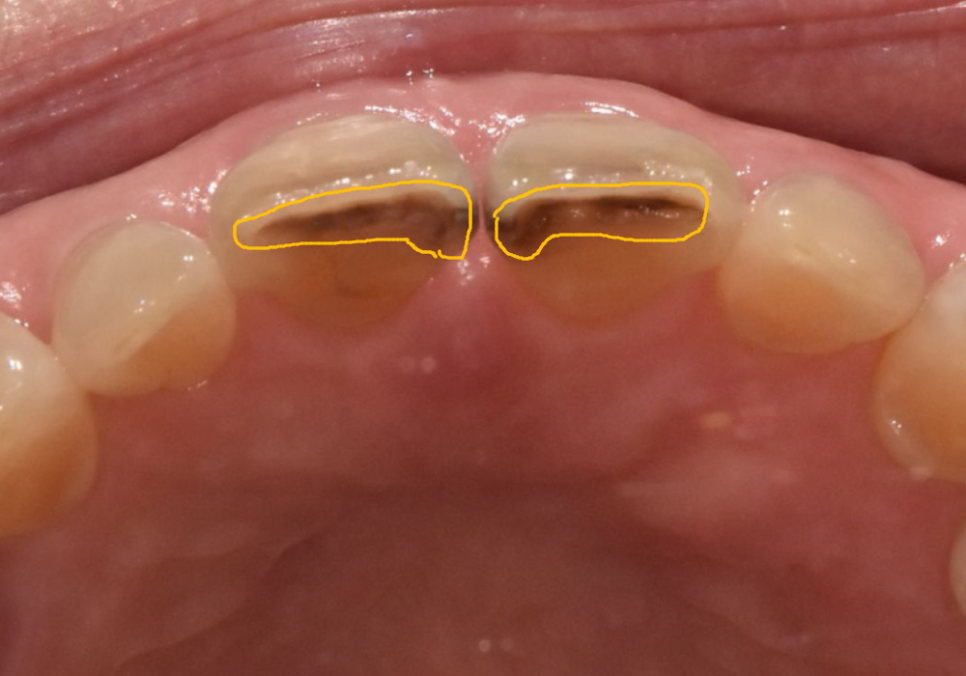

실제로 환자분의 입천장 쪽을

확인해 보니,

역시나 방어막이 사라진 마모 틈을 타

충치가 안쪽까지 깊게 퍼져 있는 모습...

결국 안전하게 치아를 보호해 주는

지르코니아 크라운으로

치료를 도와드렸어요.

앞니 사이가 벌어져 고민이셨던 부분까지

세밀하게 반영하여 자연스럽게

마무리해 드렸습니다.^^